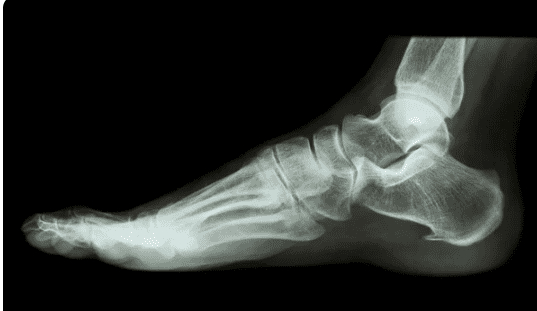

IMPORTANCE OF FOOT X-RAY -FOOT X-RAY is done to image the bones and joints of the foot. It is performed to assess the impact of injury, infective process, or congenital deformity.

Position of the X-ray –You have to put your foot on the image-capturing cassette, as advised by a technician. He’ll make two or three positions, like AP, Lateral / side view, and Oblique views, as advised by a physician.

x-ray of foot AP and Lateral views